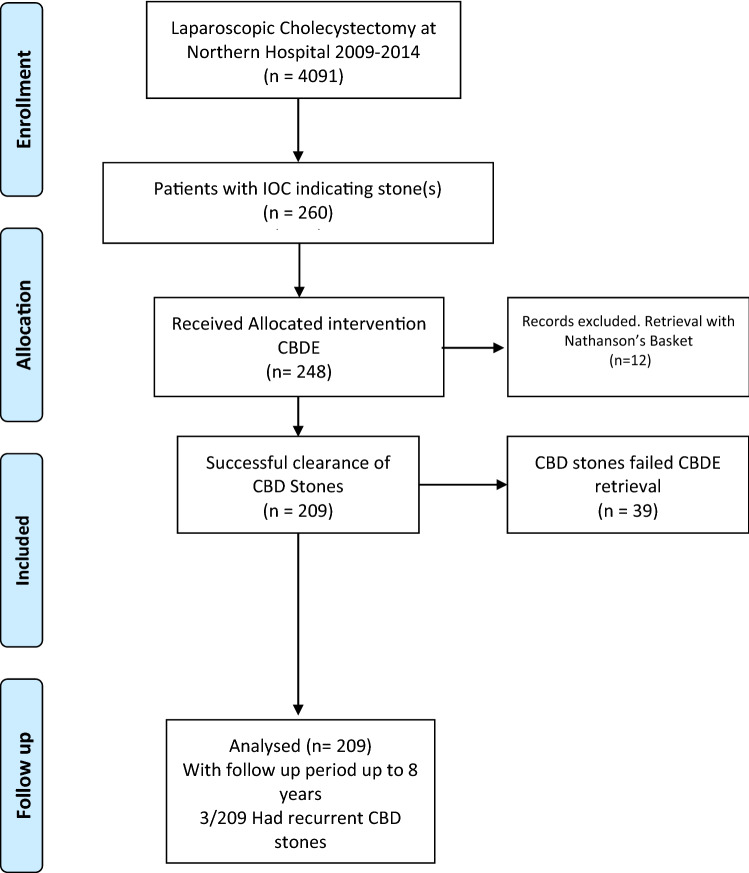

Debate still exists for the management of choledocholithiasis. The purpose of this study is to quantify the rate of recurrent choledocholithiasis post choledochoscopic bile duct exploration (CBDE) in comparison to ERCP and sphincterotomy, and to demonstrate the feasibility of this approach in a busy metropolitan hospital. Data of patients undergoing CBDE from 2009–2014 at the Northern Hospital, Victoria, Australia, was collected retrospectively. Primary outcomes were bile duct clearance rate and rate of recurrent stones post-clearance. Secondary outcomes measured were post-operative complications, laparoscopic to open conversion rate and operative time. Data of patients undergoing ERCP at the same institution was collected and compared. In total, there were 4,091 cholecystectomy cases performed from 2009–2014, of which 260 (6.3%) of patients had an intraoperative cholangiography (IOC) indicating a common bile duct (CBD) stone. Two hundred and forty-eight patients (95.3%) had a CBDE. The remaining 12 patients (4.6%) had radiological clearance, which were excluded from the study. The overall clearance rate for patients undergoing CBDE was 84% (209/248). The risk of recurrent stones up to 8 years post clearance was 2% (4/209). In the same institution, and between 1998–2012, a total of 1,148 patients underwent ERCP, of which 571 had endoscopic sphincterotomy (ES). Forty-three patients required a repeat ERCP for recurrent CBD stones with a complication rate of 7.5%. Time to recurrence ranged from 6 months to 10 years with a mean of 4.5 years. The rate of recurrence was lower in the CBDE group compared to the patients who had an ERCP (8.9% vs. 2%). CBDE is a feasible and effective method for clearance of CBD stones at the time of laparoscopic cholecystectomy. This approach, although not widely used, reduces the need for ERCP, which has inherent complications. In the longer term, this series showed a significant reduction in the rate of CBD stone recurrence.

Four thousand and ninety-one patients were admitted to the Northern Hospital for a cholecystectomy between 2009 and 2014. Mean age was 48 years old (14–98 years old). Gender distribution was female:male 70:30.

Routine cholangiogram (IOC) is performed at the time of laparoscopic cholecystectomy at this institution. Out of 4,091 patients, 260 (6.3%) had an IOC indicating bile duct stones. Two hundred and forty-eight patients (5.9%) proceeded to a CBDE, with pre-operative diagnosis listed in (Table 2). Twelve patients had their stones retrieved using radiological methods (Nathanson’s basket or Fogarty balloon). These were excluded from the study.

The PRISMA chart summarises the enrolment criteria, allocation, follow up and results analysis (Fig. 4).

Of the 248 patients that proceeded to CBDE, 209 had stones successfully cleared via a laparoscopic choledochoscopy giving a clearance rate of 84% (209/248). The risk of recurrence of CBD stones noted over these 8 years was 1.4% (3/209).